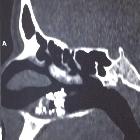

Rhinoliths are usually unilateral and solitary, and most commonly between the inferior meatus and the nasal septum.

These lesions appear as a densely calcified mass in the nasal cavity, with displacement and expansion or destruction of the adjacent bony landmarks.

Some of the remote complications include perforation of the hard palate, bony destruction, erosion of the stone into the maxillary sinus, facial spasms, or septal perforation.